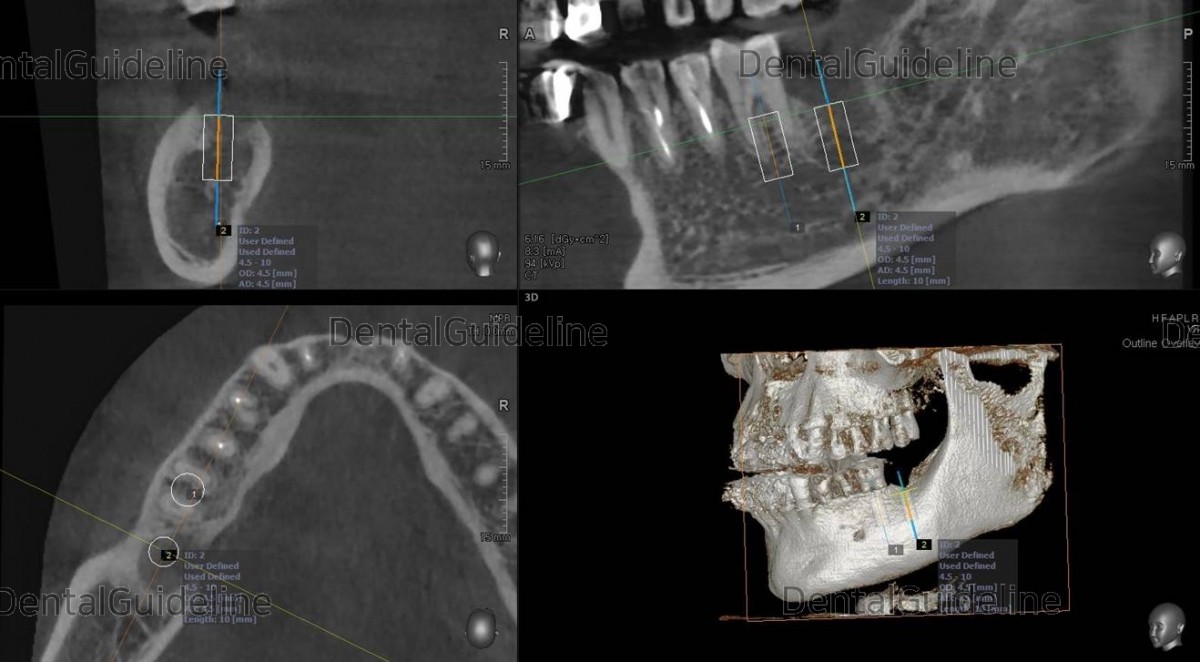

The surgery was simulated simply

![]()

A panoramic radiograph was taken. Arum NB-1 Ø5/10mm

Torque value at the 1st molar and 2nd molar zone. The fixture in the 2nd

molar showed poor initial stability despite less drilling. It was barely 10Ncm.